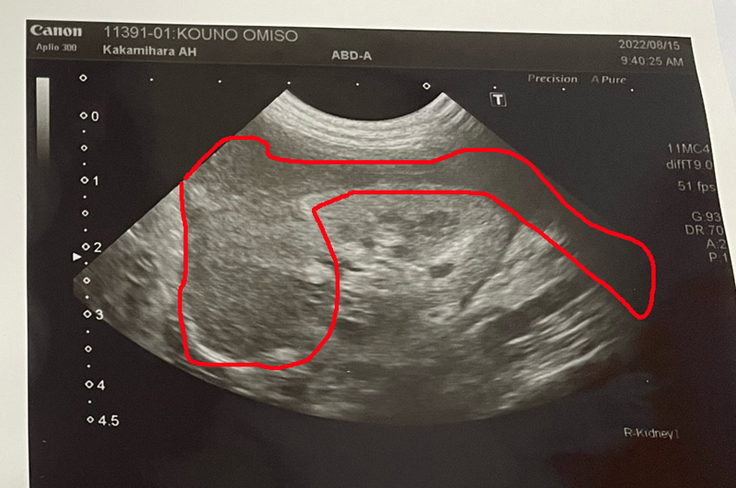

更にエコー画像では、前回腎臓の外側の黒くなっていた部分は、腫瘍が腎臓を取り巻く形になっている事が判明しました。

今まで抗がん剤治療をしてきましたが、今回の状態を見る限り、この腫瘍に対しては抗がん剤治療の限界(為すすべが無い)との見解。

この先の手段としては、手術にて摘出の話もありましたが、摘出しても腎臓周辺の腫瘍は無くなりますが、血液を通し他に転移している可能性も否定出来なく、腎臓が1つになる事で、この先の容態にも心配が。しかし今の状態では、いずれ腎臓の機能停止も考えられる事と。いずれ機能停止になる1つの腎臓。摘出し良い方向に向かうのか、ただ摘出し傷を追うだけで効果が無い状態か、この先1つだけの腎臓でどれ程命を繋げる事が出来るのか、手術は賭けになってくるとの事でした。更には最悪の場合、手術後に容態急変にて死に至る可能性も否定出来ない事もあるとのことでした。